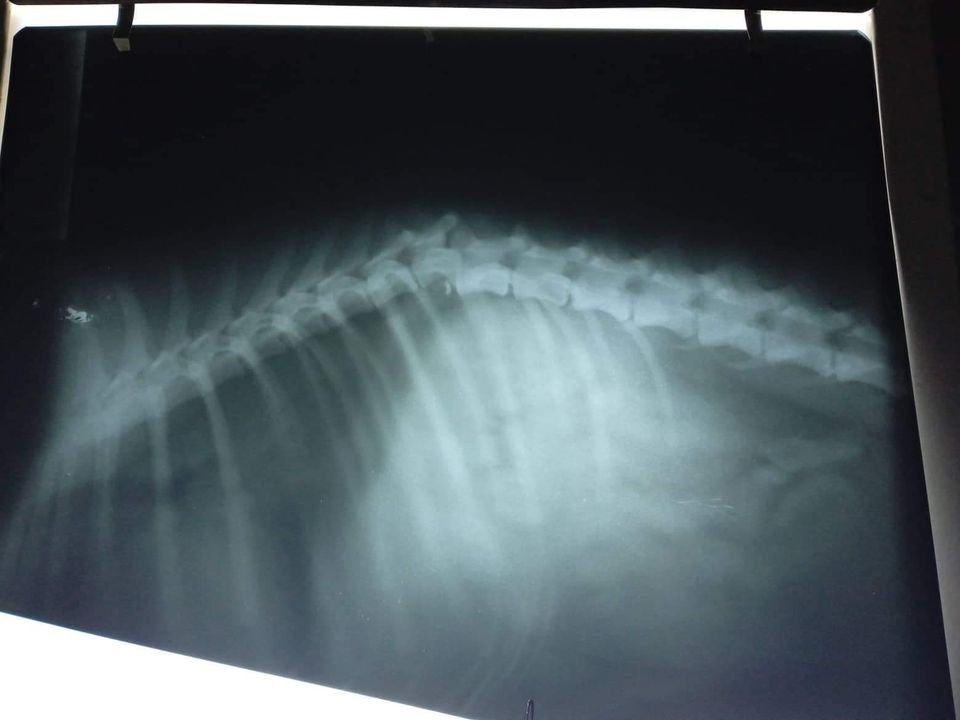

Over the years we have dealt with multiple spinal issues, but each one has a different prognosis depending on the specific vertebrae that is affected and the extent of the damage.

Doc Gama believed she has a chance of recovery with intensive laser therapy. We trust his judgement implicitly - if he says a dog needs to be put to sleep, we know that is the only viable option. If he says there is hope, we will do everything in our power to save the dog.